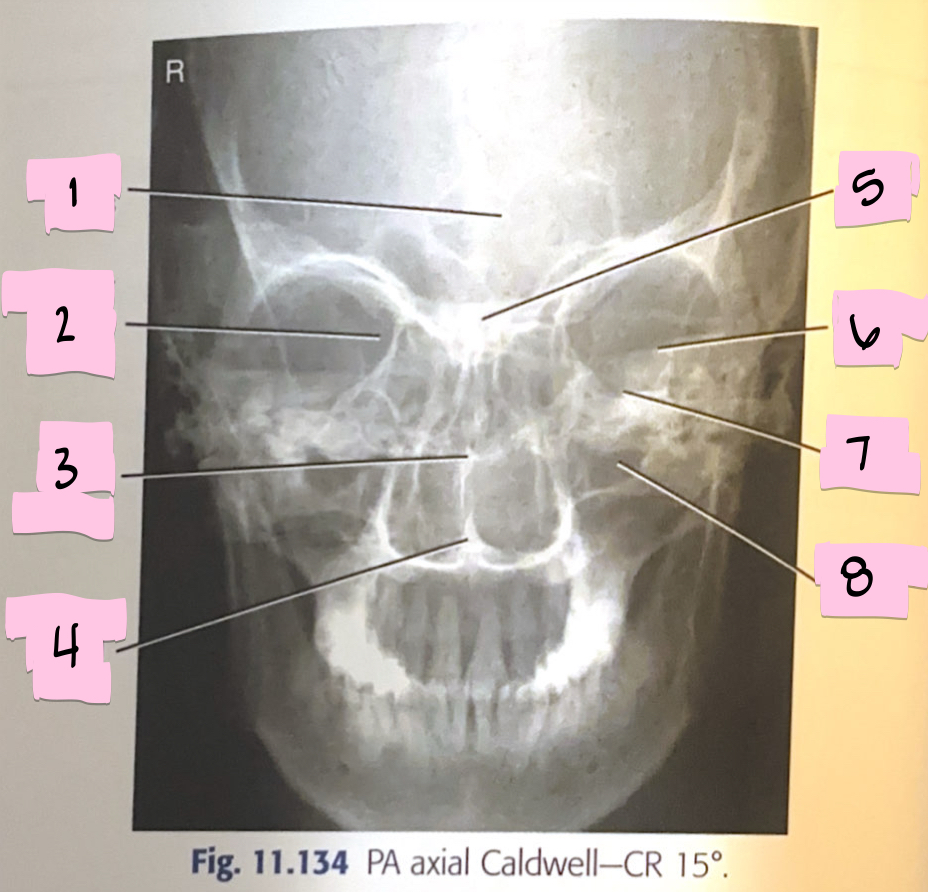

What is 1 pointing to?

Frontal sinus

What is 2 pointing to?

Superior orbital fissure

What is 3 pointing to?

Bony nasal septum

What is 4 pointing to?

Anterior nasal spine

What is 5 pointing to?

Crista galli

What is 6 pointing to?

Petrous ridge

What is 7 pointing to?

Floor of orbit

What is 8 pointing to?

Maxillary sinus